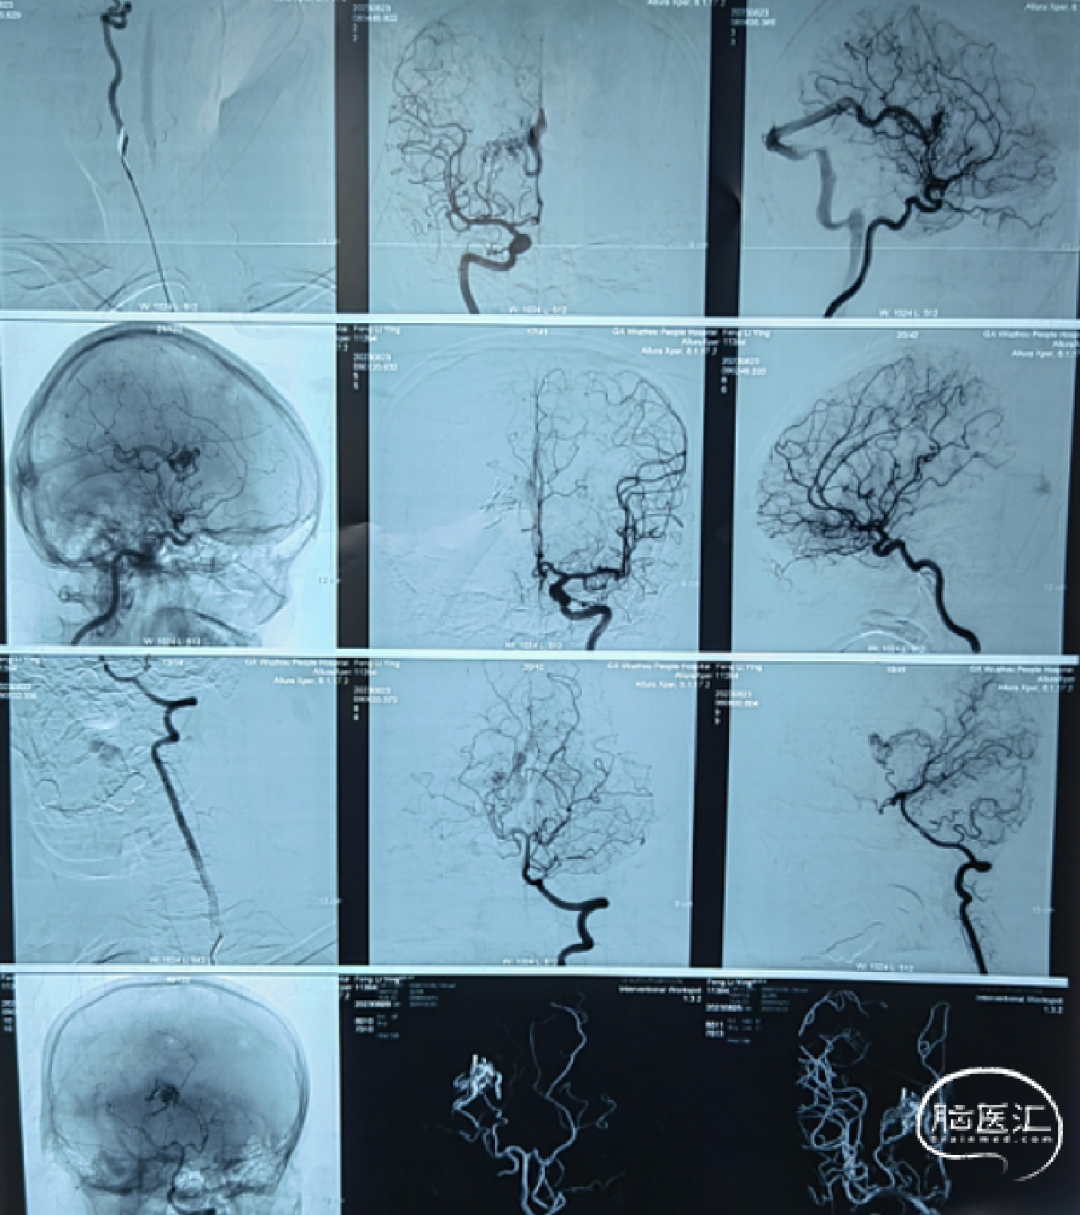

外院DSA:右侧基底节动静脉畸形

术前DSA:右侧基底节动静脉畸形,豆纹动脉供血,经大脑静脉、直窦、横窦、乙状窦引流

术前DSA